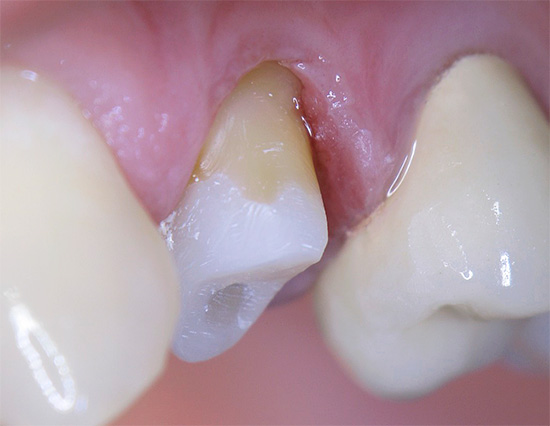

A coroa de metal-cerâmica requer um processamento significativo de esmalte de todas as 5 superfícies do dente. Dele, de fato, resta um coto, portanto, o médico deve cumprir estritamente todas as condições de trabalho: do conhecimento das zonas de segurança para impedir a proximidade de uma broca rotativa à câmara pulpar, ao uso de dicas modernas adaptadas ao arrefecimento por água e ar da área tratada por todos os lados. Se pelo menos uma condição for violada, o dente superaquece e subsequentemente começa a doer.Freqüentemente, nesses casos, o dente dói sob a coroa devido ao calor, e a dor não passa muito tempo depois de eliminar a fonte de irritação, muitas vezes se intensifica à noite.